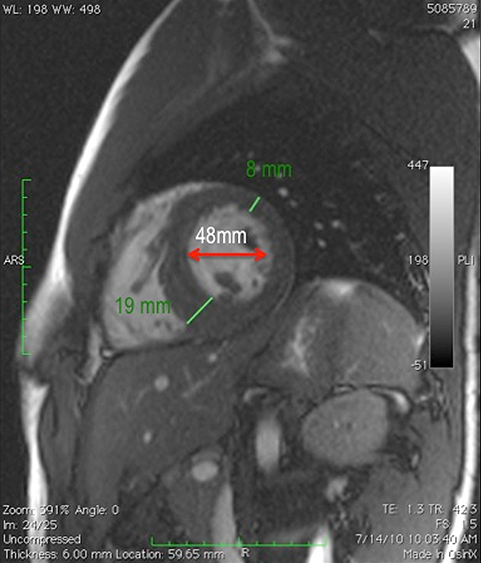

A 19-year-old college athlete with prior diagnoses of a bicuspid aortic valve and an "athletic heart" is scheduled to leave for tryouts for a professional soccer team in Spain. Independent review of his electrocardiogram (ECG) (Figure 1) prompted a closer look at his last evaluation by his pediatric cardiologist. The echocardiogram showed mild AS from a bicuspid valve aortic valve without aortic dilatation (Figures 2 and 3). His left ventricular cavity was small with abnormal papillary muscle size and position (Figure 4). Cardiac magnetic resonance imaging (MRI) was suggested and showed findings similar to the echocardiogram (Video 1); in addition there was delayed enhancement suggestive of fibrosis (Video 2). A stress test was performed, and a 3 beat run of ventricular tachycardia (VT) occurred in stage five (Figure 5). He was restricted from competitive sports and first-degree relatives were evaluated. No gene mutation was identified. His father was screened. Although he had no evidence of aortic valve disease or aneurysm formation, the patient was diagnosed with hypertrophic obstructive cardiomyopathy (HOCM) and was restricted from playing competitive soccer.